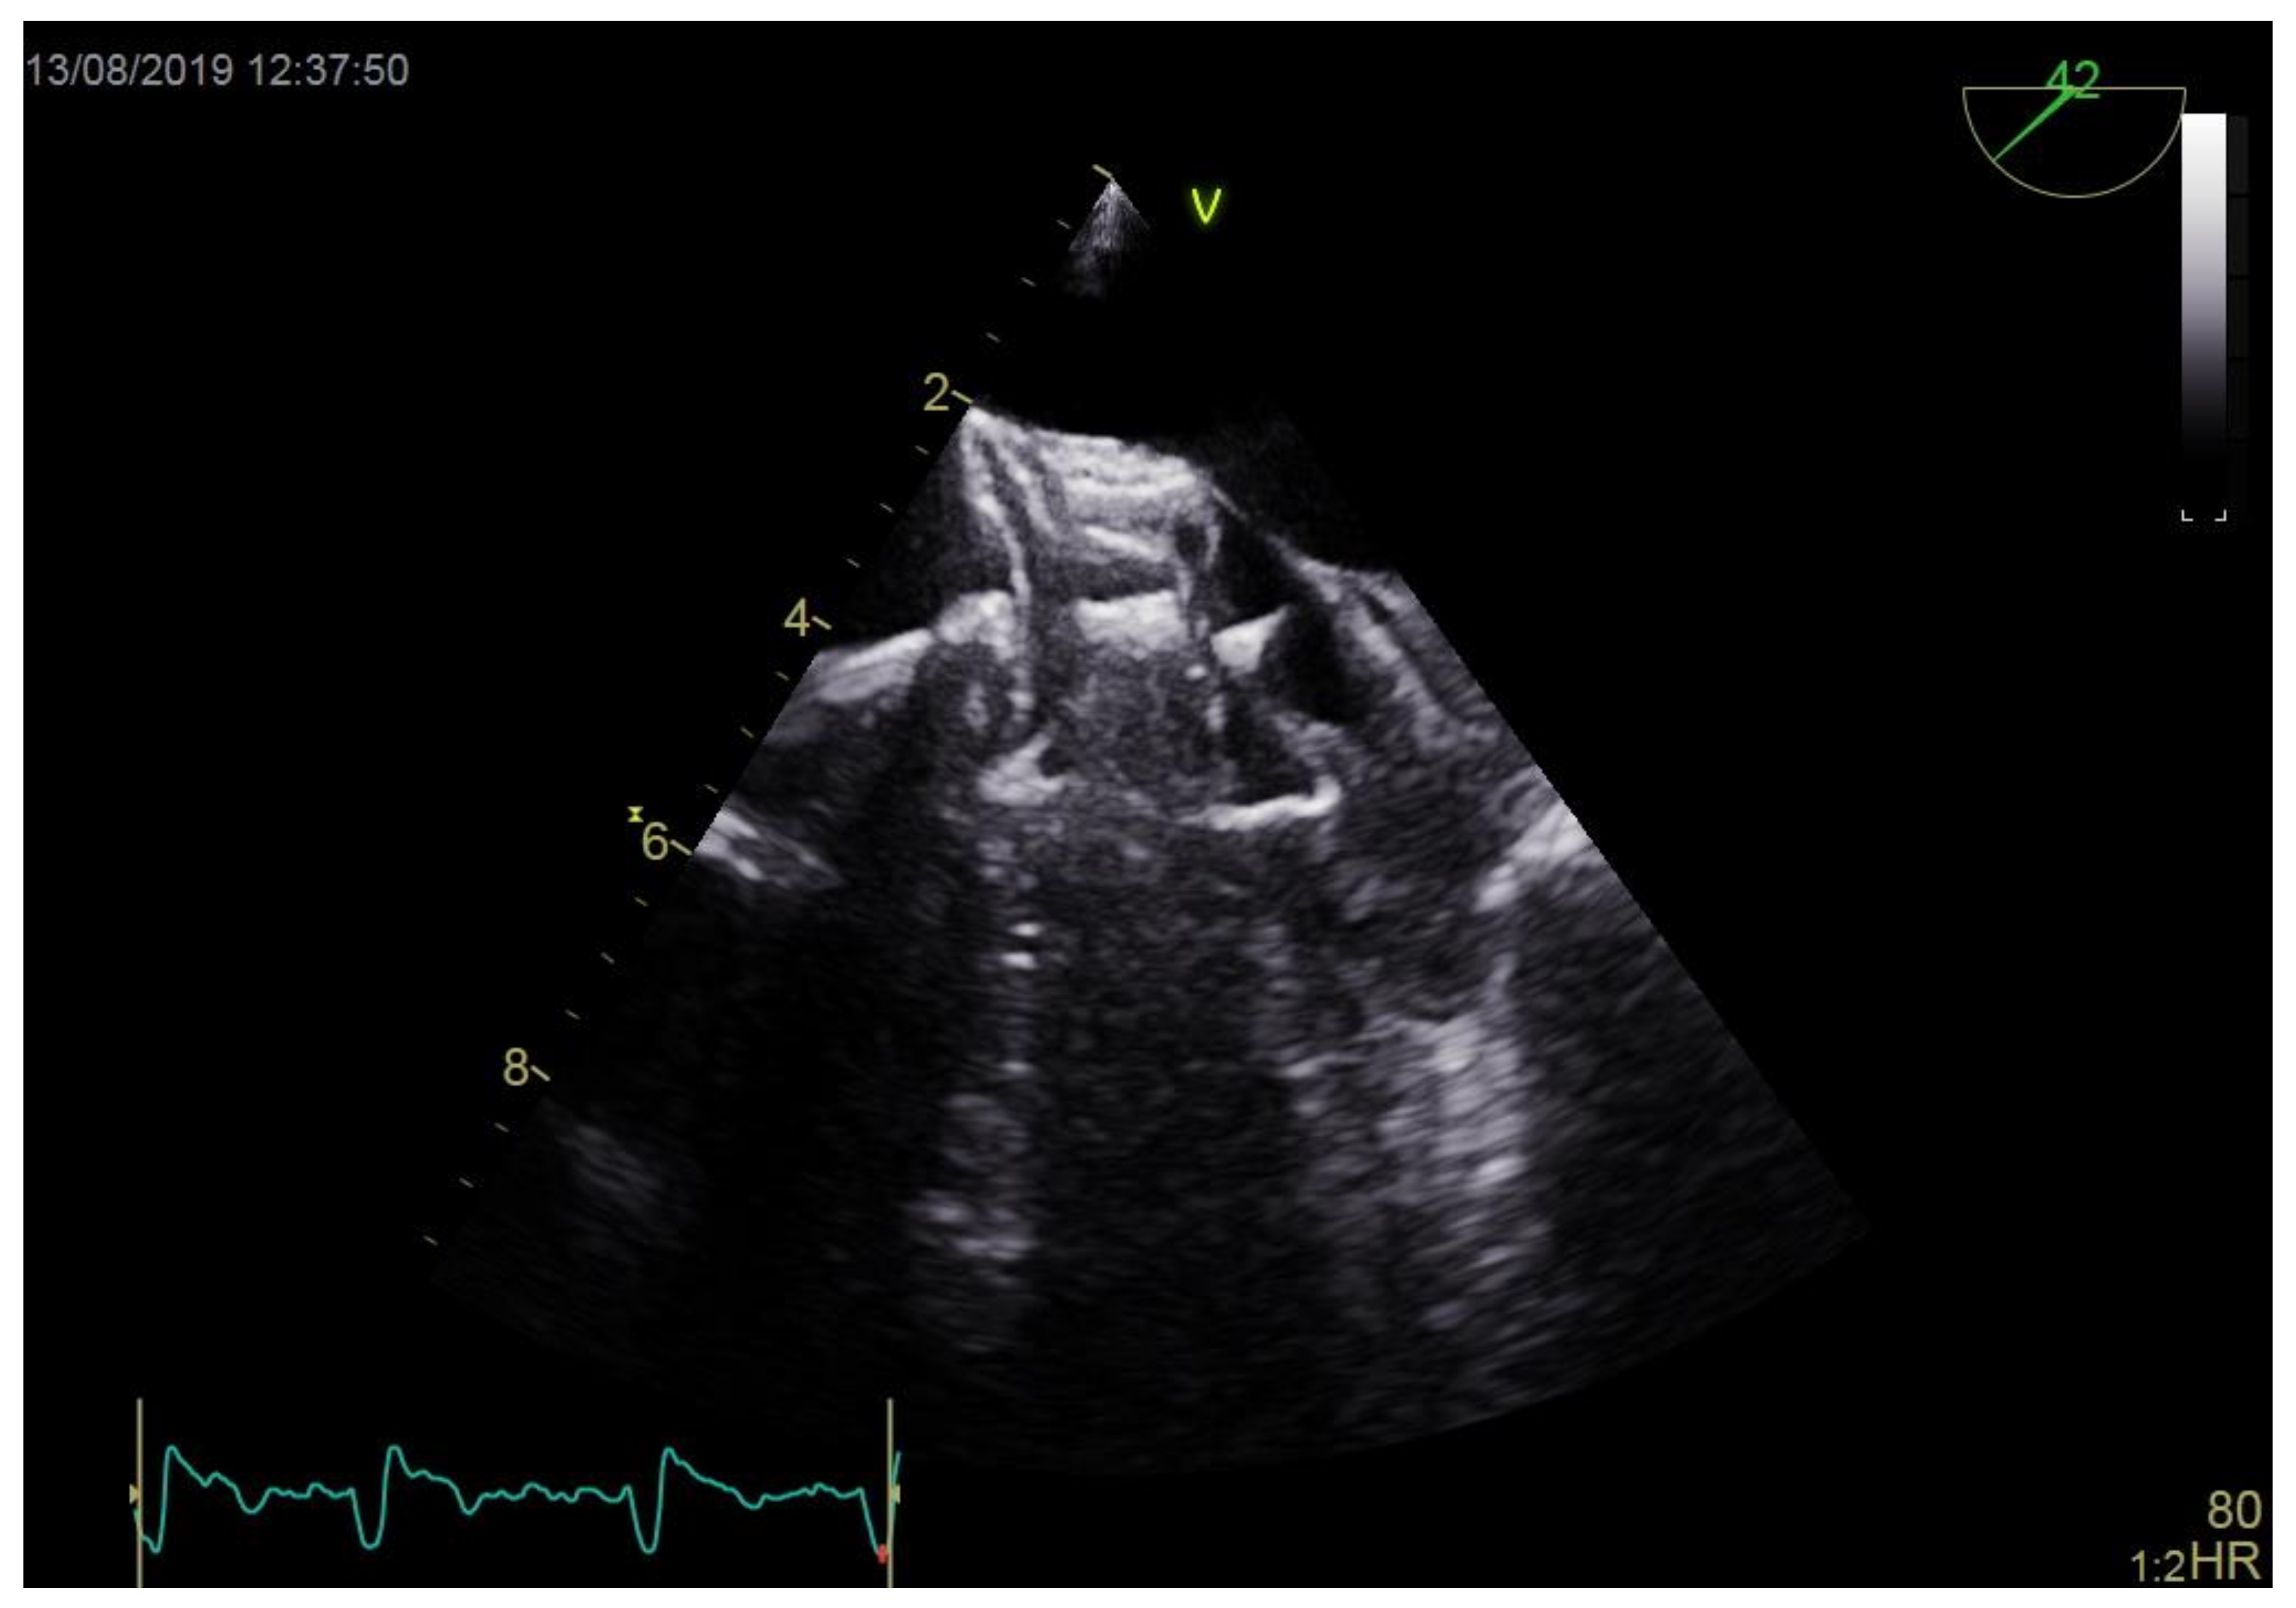

Figure 2.

Occluder in contact with left atrial appendage thrombus.

Technical details of the occluding devices used in PLAAC procedures are summarized in Table 3. Devices were successfully positioned during the first attempt in 11 (64.7%) patients. Three patients (17.6%) had the device repositioned once, and 3 other patients had the device repositioned 3 times. Implanted occluders had diameters 6.3 ± 3.9 mm larger than the LAA orifice, which accounted for 15.2 ± 3.9% of mean percentage oversizing. Eventually, occluders were implanted in appropriate positions in all patients, jailing LAAT and passing stability tests. In one individual, a residual perioccluder leak of a > 5 mm jet was revealed after the device had been deployed, but due to the high eccentricity of the LAA ostium (EI = 0.45), no better position was available. During occluder positioning in 3 patients (17.6%), the devices had direct contact with thrombi (Figure 2, Supplementary Video S2). Nonetheless, in none of these cases was the clot mobilized or were clinical signs of intraprocedural thromboembolic events observed.